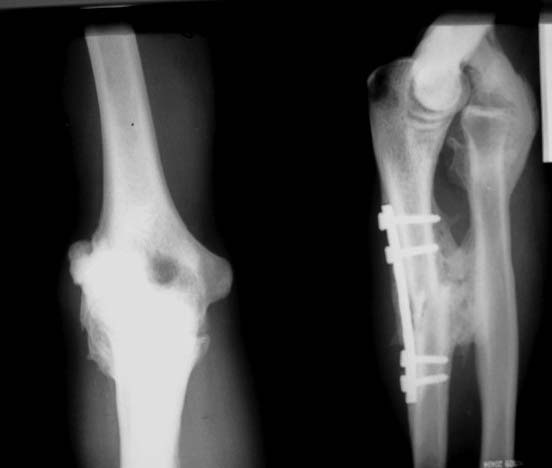

> Мужчина 27 лет, травма год назад - удар по предплечью электропоездом.В ЦРБ

> - остеосинтез

> локтевой кости, вероятно - открытое вправление вывиха головки лучевой

> кости (выписки нет,

> но пациент говорит, что были металлические спицы и есть п/операционный

> рубец в проекции

> головки лучевой кости). В настоящее время: движения в локтевом суставе

> отсутствуют.

> предплечье находится в положении сгибания 160*. Хочется услышать мнения об

> объеме

> оперативного вмешательства, во сколько этапов его проводить.

Залечен ужасно. Видимо пластину поставили в вывихе головки и забыли про

пациента. А деньги видимо взяли.

С такой костной мозолью уже трудно бороться, а вот автора следовало бы

поучить как следует прежде чем разрешать оперировать больных.